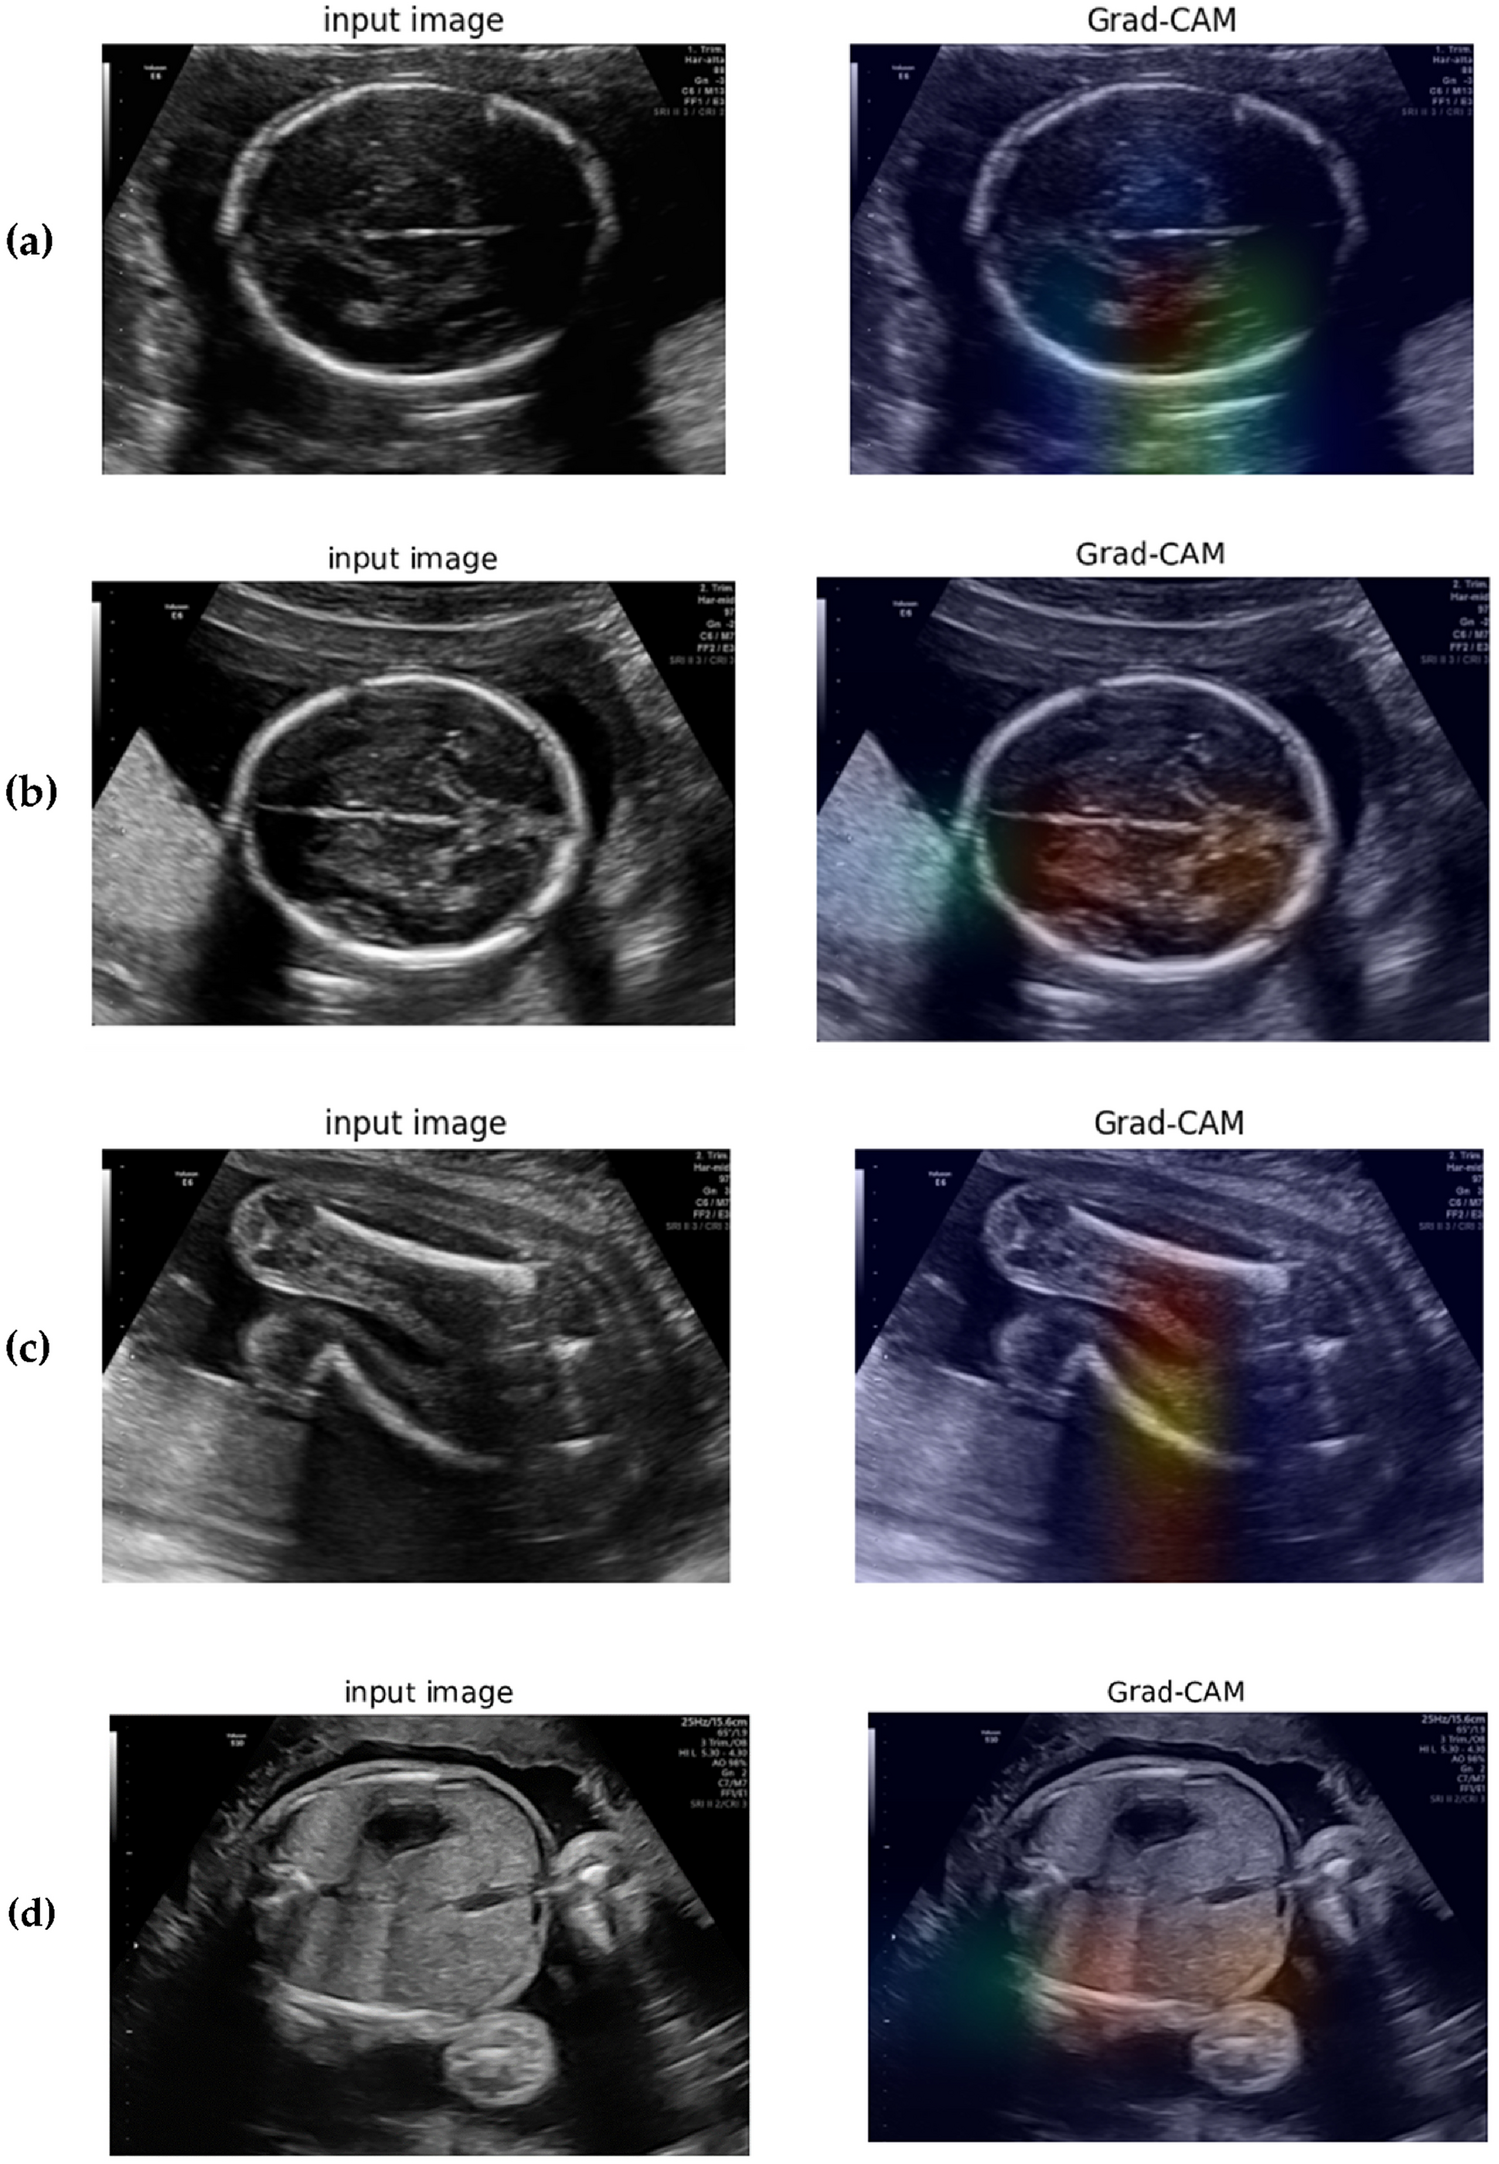

Figure 10

Visualization of fetal organ detection using Grad-CAM with DensNet model architecture. (a) and (b) Represent the class activation map for fetal brain detection, (c) shows the class activation map for fetal femur detection, and (d) shows the class activation map for fetal abdomen detection.